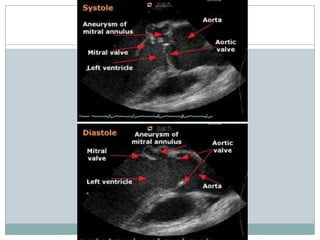

Diagnostic criteria for vegetations

** Valvular vegetation is defined as "a discrete mass of echogenic material adherent at

some point to a leaflet surface and distinct in character from the remainder of the

leaflet" based upon the following characteristics:

Texture — gray scale and reflectance of myocardium

Location — upstream side of the valve in the path of the jet or on prosthetic material

Characteristic motion — chaotic and orbiting; independent of valve motion

Shape — lobulated and amorphous

Accompanying abnormalities - abscess and pseudoaneurysm, fistulae, prosthetic

dehiscence, paravalvular leak, significant preexisting or new regurgitation

** Vegetations also characteristically prolapse into the upstream chamber: mitral

vegetations into the atrium in systole and aortic vegetations into the left ventricular

outflow tract during diastole.

**Vegetations tend to flank the regurgitant jet.